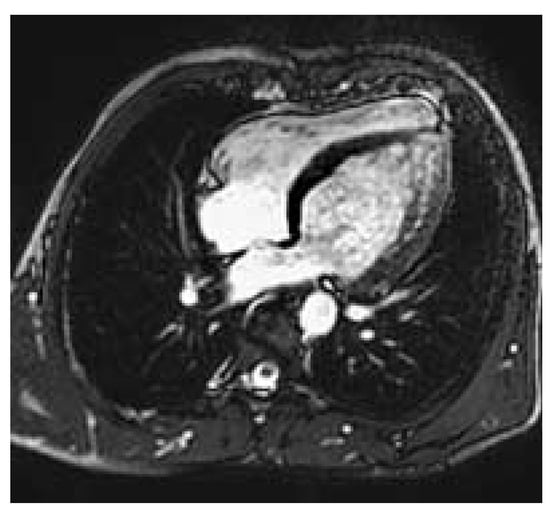

Figure 2. Severe postductal coarctation with poststenotic saccular aneurysm and extensive collateral formation (CMR 3D contrast enhanced acquisition).

A cardiovascular magnetic resonance study (CMR) was performed at our institution in order to assess the exact location, the degree and severity of the aortic stenosis and to rule out associated congenital anomalies. CMR showed a normal left ventricular mass (181 g, 95.3 g/m2, [normal: 91 ± 11 g/m2]), a moderately reduced left ventricular ejection fraction of 37.6%, a diffuse, apically pronounced hypokinesia with apical trabeculations (fig. 1), and no late contrast enhancement. In CMR, the aortic root was slightly dilatated (40 mm), the ascending aorta was normal but the aortic arch was slightly hypoplastic. The proximal part of the descending aorta showed a severe postductal stenosis (fig. 2) of 28 mm in length, a small poststenotic saccular aneurysm (confirmed by surgery, fig. 3), and an extensive collateral vascular system through the subclavian, scapular, internal thoracic, and intercostal arteries. The origin and proximal course of the coronary arteries as well as the pulmonary venous return were normal.

Postductal aortic stenosis is a typical narrowing of the aortic lumen with an incidence of 1:6000 live births. It may occur in patients with Turner’s syndrome, and may be associated with a ventricular septal defect, the Shone syndrome, and cerebral aneurysms in the circle of Willisi. The most frequent form is the postductal one (98%).

Early detection of this malformation is crucial. In patients operated before age 14, the 20-year survival of postductal coarctation after operation is 91%, after the age of 14 only 79% []. The major causes of death are aortic rupture and cerebral hemorrhage.

In summary, surgery is the preferred method in severe coarctation, especially when signs of aortic wall weakness, a postductal saccular aneurysm, and a dilatation of the aortic root are already present. Percutaneous dilatation is effective solely in mild coarctation and in recurrent coarctation following surgical repair. In severe coarctation percutaneous dilatation remains controversial because of the risk of incomplete relief of obstruction or aneurysm formation []. Furthermore, in subjects with a hypoplastic aortic arch associated with coarctation, as in our patient, percutaneous intervention is not a feasible approach [].